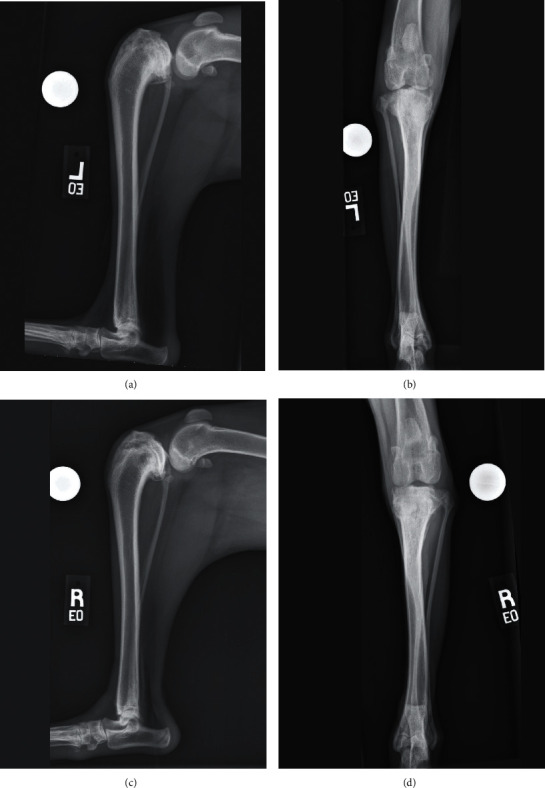

一只9个月大的混血狗因双侧胫骨近端畸形导致胫骨平台角过大和颅交叉韧带功能不全。右侧骨盆肢体的初始手术处理是通过颅骨闭合楔形骨切除术完成的。平台水平不高导致半月板撕伤,在胫骨平台水平截骨手术中得到解决。左侧骨盆肢体在一次手术中使用三维(3D)虚拟手术计划和定制的3D打印手术指南进行联合颅合楔形骨切除术和胫骨平台平切术。术后左胫骨的三维分析显示,手术结果的准确性在虚拟手术计划的2°以内。手术后,狗出现了短暂的II/IV级左内侧髌骨脱位,但最终实现了完全的功能恢复,并在手术后46个月积极参与左骨盆肢体的竞技敏捷性工作。

A 9-month-old mixed-breed dog was presented for bilateral proximal tibial deformity resulting in an excessive tibial plateau angle and cranial cruciate ligament insufficiency. Initial surgical management of the right pelvic limb was done by performing a cranial closing wedge ostectomy. Inadequate leveling of the plateau resulted in a postliminal meniscal tear which was addressed during a revision tibial plateau leveling osteotomy. The left pelvic limb was managed in a single-session surgery using three-dimensional (3D) virtual surgical planning and custom 3D-printed surgical guides to perform a combined cranial closing wedge ostectomy and tibial plateau leveling osteotomy. Postoperative 3D analysis of the left tibia revealed the accuracy of the surgical result within 2° of the virtual surgical plan. The dog developed a transient grade II/IV left medial patellar luxation following surgery but ultimately attained a full functional recovery and was actively engaged in competitive agility work 46 months following surgery on the left pelvic limb.